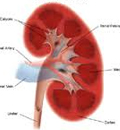

6. 급/만성 신부전 (Acute & Chronic kidney disease)

신장기능저하증 (Renal insufficiency)

- 급성 신부전 (acute kidney injury)

중독, 감염, 요도 폐색, 탈수에 의한 허혈성 변화 등으로 인하여 갑작스럽게 신장 기능이 감소하여 발생한다. 수액처치, 전해질 교정 등으로 치료가 진행되지 않을경우 응급상황으로 악화될 수 있습니다.

만성 신부전 (chronic kidney disease)

신장 기능저하증(renal insufficiency) 단계를 지나 신장 기능의 손상(75%이상)으로 인해 뚜렷한 임상증상을 보이는 단계이다. 만성 신부전 상태의 고양이는 식욕부진, 체중감소, 탈수, 다음/다뇨 등의 증상을 보인다. 신우신염, 중독 등에 의해서도 발생할 수 있으나 주로 노령성으로 발생하게 된다. 혈액검사 상 크레아티닌 수치와 BUN 수치의 증가를 통해 진단할 수 있으며 뇨검사, 초음파 검사 등의 추가적인 검사가 필요하다. 신부전은 고혈압, 빈혈 등의 추가적인 질환을 유발하므로 장기간의 수액처치, 약물치료, 단백질/인 제한식이 등이 필요하다.

신장 기능저하증 (renal insufficiency)

신부전의 진행 과정의 한 단계로서 크레아티닌 수치가 정상이상으로 증가하지만 무증상 또는 경미한 증상만을 보인다. 일반적으로 만성 신부전 증세가 나타나기전, 수 개월 동안 지속된다. 점진적인 식욕감소, 체중감소, 물섭취량 및 소변량의 증가를 보이며 노화과정의 한 부분이라고 생각하여 지나치기 쉽다. 수액처치, 약물치료 등으로 수치가 정상으로 돌아오더라도 정상적인 신장상태를 의미하는 것은 아니므로 주기적인 검사와 지속적인 관리가 필요하다.